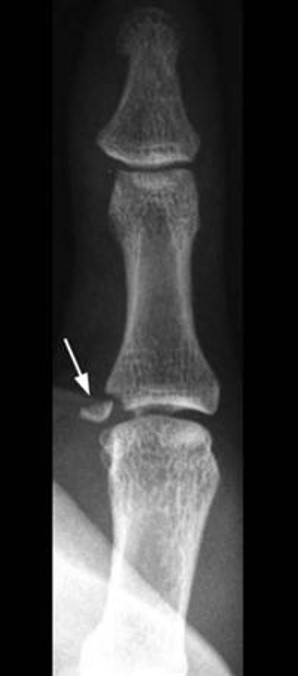

Ulnar collateral ligament avulsion fracture

An ulnar collateral ligament injury of the thumb occurs when the thumb is forcibly stretched away from the hand causing a strain, partial or full thickness tear of the ligament or an avulsion fracture.

An x-ray is usually recommended to confirm if a fracture is present. An ultrasound or MRI may also be used to confirm the extent of the injury to the ulnar collateral ligament.